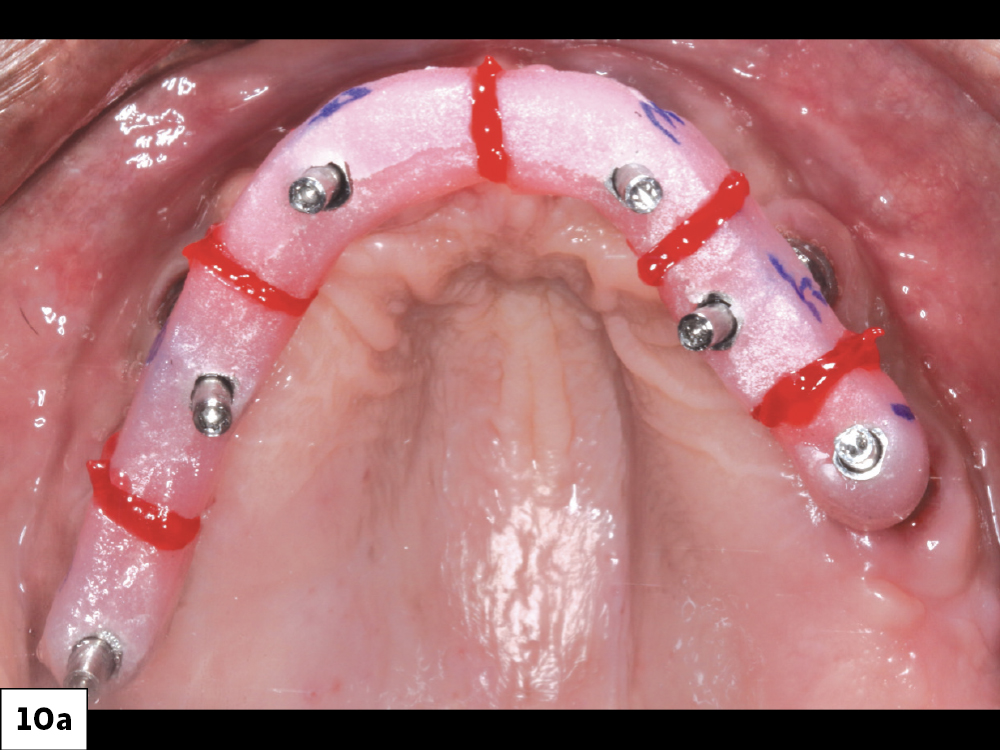

Figures 10a, 10b: The implant verification jig (IVJ) process helps ensure the accuracy of the master model. After luting the individual pieces of the IVJ together intraorally, I picked them up in the final impression.  The provisional as well as the final full-arch BruxZir® Implant Prosthesis used this master cast for fabrication.